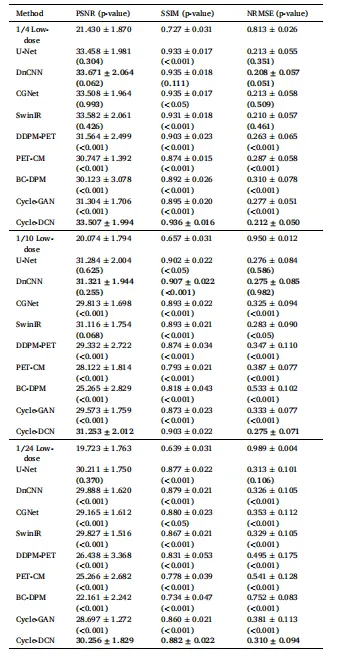

4.1. Quantitative evaluations

4.1.1. PSNR, SSIM, and NRMSE comparison

The proposed Cycle-DCN model was systematically compared with several established image denoising and restoration methods, including widely used U-Net, classic denoising model DnCNN (Zhang et al., 2017), the more recent image restoration model CGNet (Ghasemabadi et al., 2024), the Swin Transformer-based SwinIR, CycleGAN, and three diffusion-based approaches: DDPM-PET, PET-CM, and BC-DPM. Table 1provides the quantitative results, showing the mean, standard deviation, and statistical significance based on paired t-tests for each evaluation metric. Fig. 4(a) presents a visual comparison of a representative slice across the nine models, along with the corresponding full-dose and low-dose images at three different dose levels.For ¼ low-dose images, the PSNR, SSIM, and NRMSE metrics are comparable across all evaluated models. While DnCNN and SwinIR slightly outperforms Cycle-DCN in some measures, these differences are not statistically significant (p > 0.05). In contrast, for the more challenging 1/24 low-dose images, Cycle-DCN achieves superior metric values. The three diffusion-based methods—DDPM-PET, PET-CM, and BC-DPM—consistently yielded inferior performance under all the three low-dose conditions. As shown in Fig. 4(a), U-Net and DnCNN result in excessive smoothing, leading to increased deviation from the full-dose images at lower dose levels, with small sulci becoming nearly indistinguishable. However, Cycle-DCN remains closer to the full-dose images, demonstrating better robustness. In the enlarged views in Fig. 4(b), Cycle-DCN uniquely preserves brain structures such as sulci and gyri, producing visual outputs more consistent with full-dose images compared to other models. Among the three diffusion-based methods, DDPM-PET produced visually promising results across all dose levels. However, the performance of BC-DPM (trained unconditionally) and PET-CM (with two-step sampling) deteriorated rapidly as the dose decreased, resulting in significantly degraded image quality.

4.1 定量评估 4.1.1 峰值信噪比(PSNR)、结构相似性指数(SSIM)及归一化均方根误差(NRMSE)对比 将所提Cycle-DCN模型与多种已有的图像去噪和恢复方法进行了系统对比,包括广泛使用的U-Net、经典去噪模型DnCNN(Zhang等,2017)、较新的图像恢复模型CGNet(Ghasemabadi等,2024)、基于Swin Transformer的SwinIR、CycleGAN,以及三种基于扩散的方法(DDPM-PET、PET-CM和BC-DPM)。表1给出了定量结果,包括各评估指标的均值、标准差以及基于配对t检验的统计显著性。图4(a)展示了九种模型在三个不同剂量水平下,代表性切片的视觉对比,同时呈现了对应的全剂量和低剂量图像。 对于¼低剂量图像,所有评估模型的PSNR、SSIM和NRMSE指标表现相当。尽管DnCNN和SwinIR在部分指标上略优于Cycle-DCN,但这些差异无统计学意义(p > 0.05)。相比之下,在更具挑战性的1/24低剂量图像中,Cycle-DCN取得了更优的指标值。三种基于扩散的方法(DDPM-PET、PET-CM和BC-DPM)在所有三个低剂量条件下均表现出持续劣势。如图4(a)所示,U-Net和DnCNN存在过度平滑问题,导致在低剂量水平下与全剂量图像的偏差增大,细小脑沟几乎无法区分。而Cycle-DCN始终更接近全剂量图像,展现出更强的鲁棒性。在图4(b)的放大视图中,Cycle-DCN独特地保留了脑沟、脑回等脑部结构,生成的视觉结果比其他模型更接近全剂量图像。在三种基于扩散的方法中,DDPM-PET在所有剂量水平下均产生了视觉上较理想的结果,但无监督训练的BC-DPM和两步采样的PET-CM的性能随剂量降低迅速下降,导致图像质量显著退化。

Table 1 Quantitative Comparison of Mean PSNR, SSIM and NRMSE among DifferentModels on the Test Dataset.

表1 不同模型在测试数据集上的平均峰值信噪比(PSNR)、结构相似性指数(SSIM)及归一化均方根误差(NRMSE)定量对比